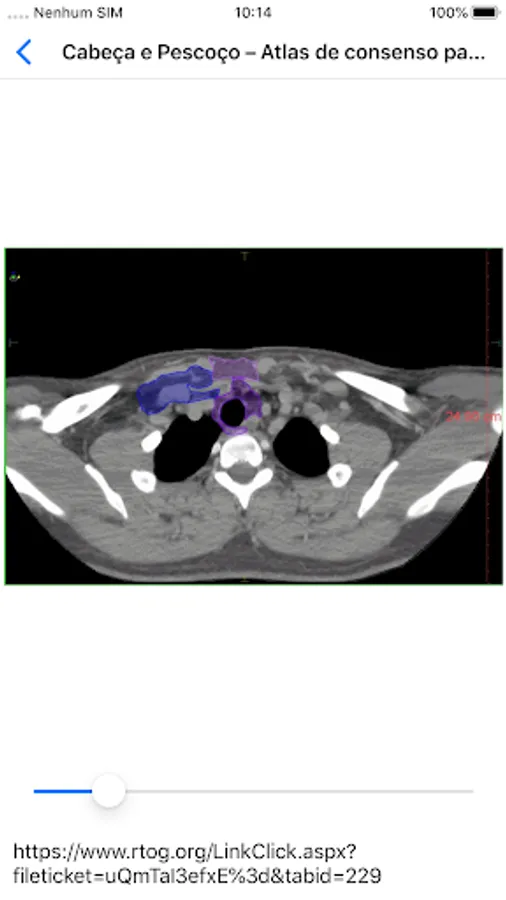

Radio ICESP Screenshots